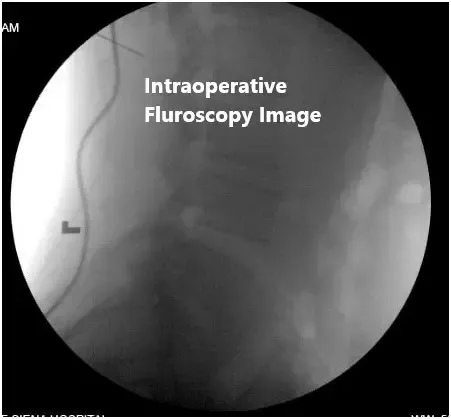

- Uso de fluoroscopia dirigida por médicos.

El paciente fue trasladado al quirófano, donde se indujo anestesia general. La colocaron para cirugía en el vientre. Se administró antibiótico preoperatorio. La incisión se realizó tras localización con fluoroscopia sobre los niveles L2 a L4. Hicimos una incisión en la línea media sobre los procesos espinosos y continuamos la disección utilizando cauterización de Bovie en el plano avascular. Aplicamos nuestros separadores auto-retenibles para separar los bordes del músculo y la piel y logramos la hemostasia con cauterización bipolar.

Imágenes fluoroscópicas intraoperatorias

Nos preocupaba esto antes de la operación, dado el nivel de dolor de espalda y anterolistesia del paciente en ese nivel, así que hicimos una incisión en ese punto para hacer una fusión no instrumentada de L2 a L3, como se había comentado con el paciente. Luego expusimos los procesos transversales de L2 y L3 y entramos en el triángulo de Kambin en el extremo lateral del nivel L2-3 para entrar en el espacio discal y realizar discectomía.